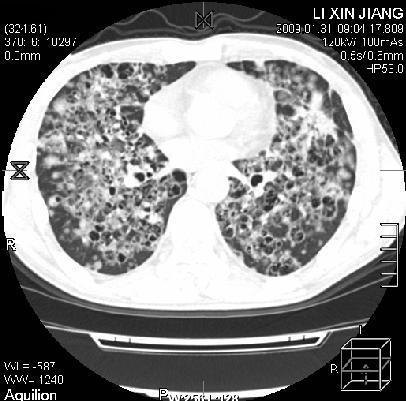

标题: CT18283:呼吸困难,明显喘息样呼吸 [打印本页]

呼吸困难,明显喘息样呼吸2个月

间质性肺病!还能用多久?

多为霉菌感染。

考虑两肺机遇性感染。

卡孢子虫肺炎(建议试验室查hiv,呼吸道分泌物找卡孢子虫)

机遇性感染,间质性病变

考虑:间质性病变伴两肺机遇性感染。

间质纤维化伴支扩。原因?

支持考虑:间质性病变伴两肺机遇性感染。

考虑 间质性病变伴两肺机遇性感染。